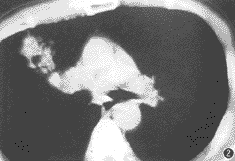

第35例——右肺门斑片状致密影

患者男性 ......